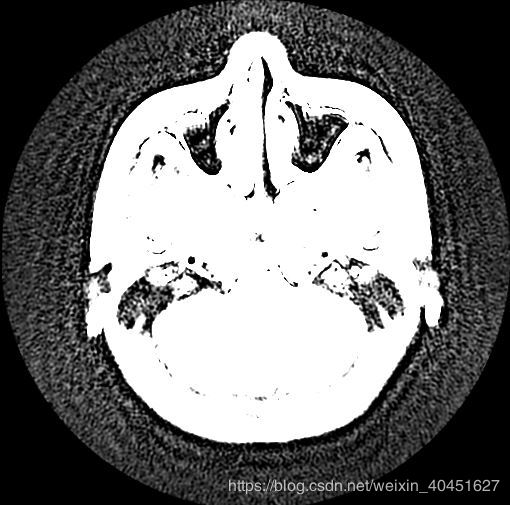

效果如圖所示:

但真實的圖像是:

顯然顏色是有區別的.導致這種差別的原因是pyplot函數使用的cm也就是'color map' 是簡單的'bone' 并不能滿足醫學圖像的要求.